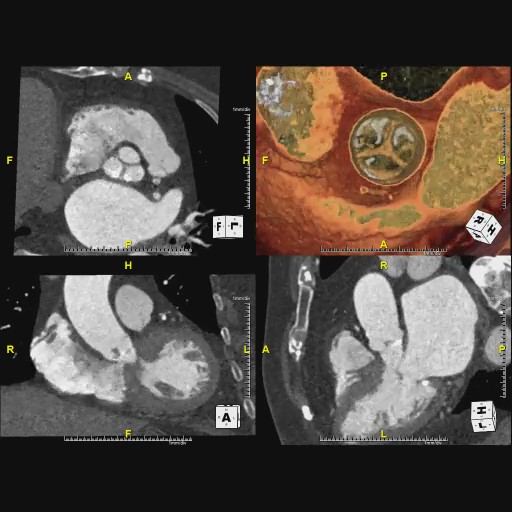

Amazon.com: CT冠動脈造影実践学: 9784498013568: unknown, 冠動脈CTによる狭心症の診断,

冠動脈CTによる狭心症の診断, 沖縄県医師会_沖縄県医師会報(2013年3月号),

沖縄県医師会_沖縄県医師会報(2013年3月号), 放射線 CT - 榊原記念病院,

放射線 CT - 榊原記念病院, CT装置|徳島赤十字病院,

CT装置|徳島赤十字病院, 320列面検出器CTによる新しい冠動脈CT技術 吉岡邦浩(岩手医科,